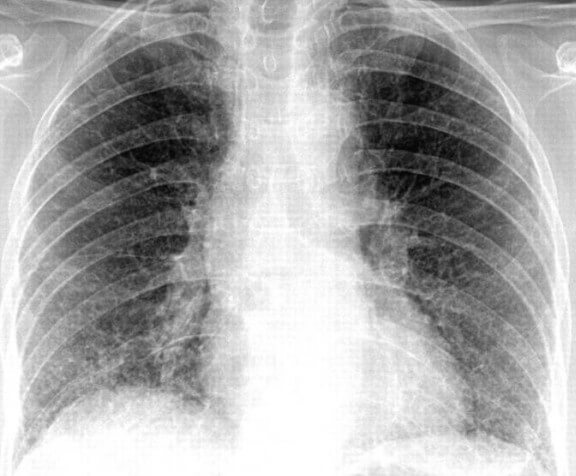

На снимке видны отдельные небольшие очаги поражения ( 1-1,5 см), расположенные в одном из легких (при билатеральной форме – в обоих). Заметным в данном случае будет расширение корней легких из-за наполнения жидким экссудатом.

Снимок при очаговой пневмонии